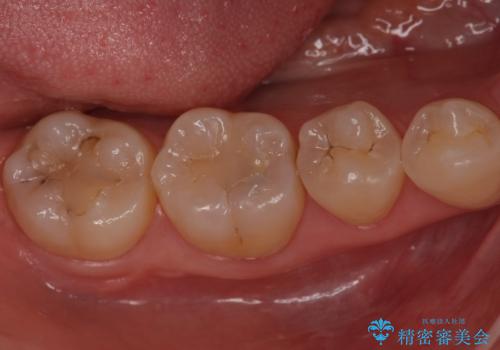

奥歯が黒く、心配。ゴールドインレーで修復

- 奥歯に以前プラスチックの樹脂で虫歯治療を行った患者様です。

歯と樹脂の隙間が黒くなってきていて若干虫歯になっていました。

樹脂は長期的な予後が悪いため、樹脂を外してゴールドインレーに置き換えました。

樹脂下の虫歯は除去しています。

樹脂の治療は1回で終わって簡単ではありますが、劣化により今回のように歯と詰め物の隙間が出来やすく、また、プラスチック自体も割れやすいため長期的な予後が見込めません。

今回は、虫歯が進行したというよりは予防的な意味も含めて、金属で丈夫な適合の良いゴールドインレー(PGAインレー)による修復治療を行うことにしました。